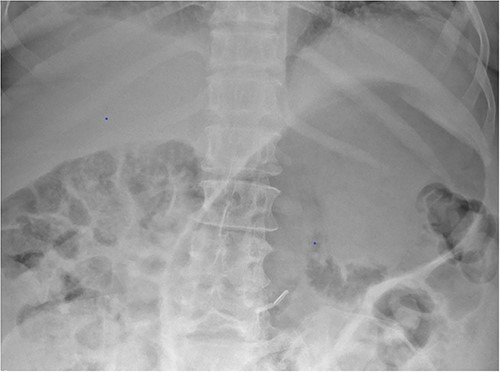

Plain film radiograph of the abdomen demonstrating a distended and gas-filled stomach.

Based on the clinical and radiological picture, acute gastric dilatation was diagnosed, presumed secondary to a combination of opioid analgesia and gastric dysmotility from Parkinson’s disease. A nasogastric tube was introduced, intravenous fluids were given, and a venous blood gas was performed, which showed pH of 7.46 and lactate 1.0 mmol/L. An urgent CT scan of the abdomen and pelvis with intravenous contrast was performed; this demonstrated there had been interval reduction of the portal venous gas (Fig. 3), with only minor residual gas seen at the periphery of the left lobe of the liver and the gastric fundal wall. No other radiological features of visceral ischaemia within the abdomen were observed, with the coeliac axis and the collaterals from the phrenic arteries and superior mesenteric artery all patent.